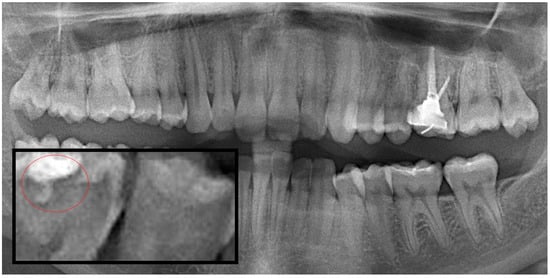

Figure 1.

Panoramic radiography and segmented interproximal caries, red circle shows the caries.